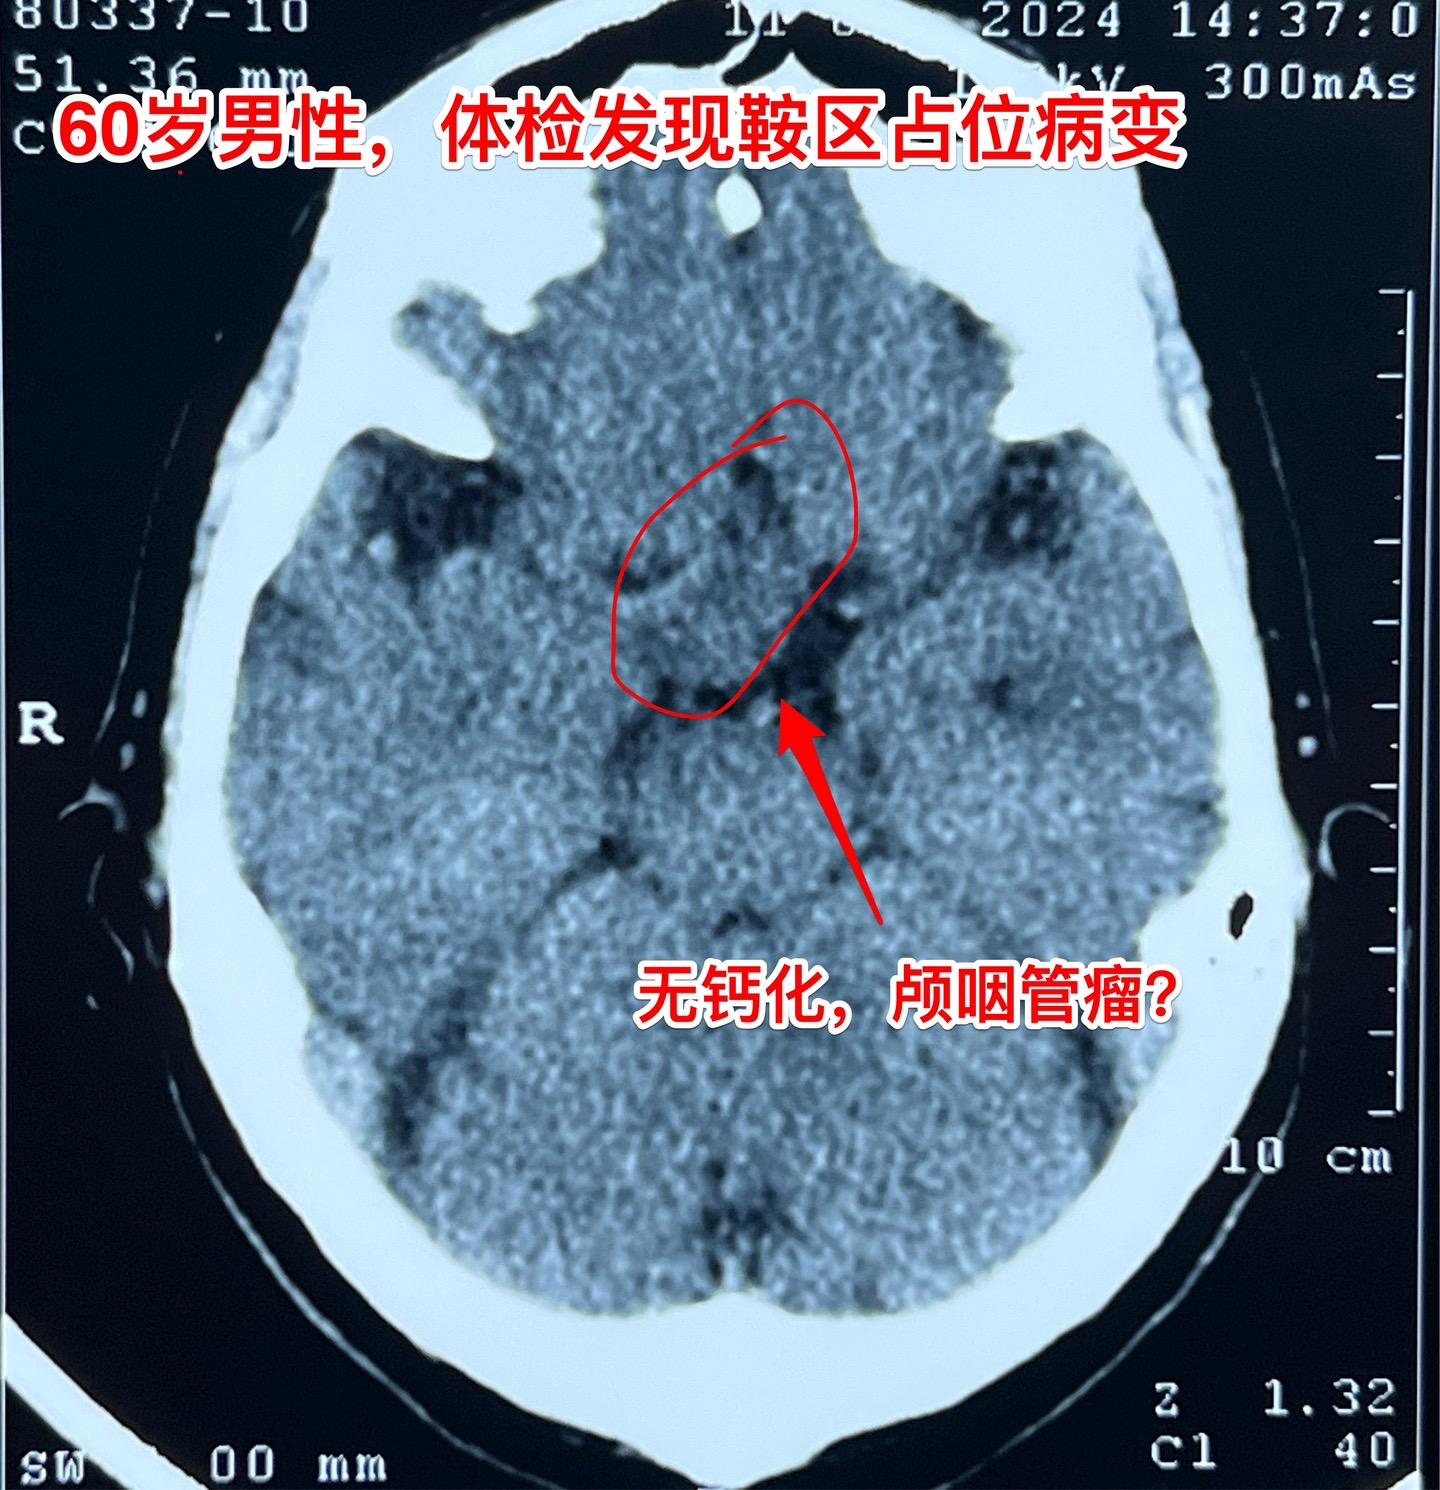

颅咽管瘤与拉克氏囊肿的鉴别不容易。60岁男性,偶然因头痛作体检发现鞍区肿瘤,怀疑为颅咽管瘤。病人无明显的视力下降。肿瘤体积不小了,CT也没有看见钙化。 到底是颅咽管瘤还是拉克氏囊肿? 2024年6月17日作了开颅手术。手术中看见病灶呈囊性,囊壁边界清楚,内有胆固醇结晶体,其周围脑实质有黄染。垂体柄得到保留。 手术后病理报告为:拉克氏囊肿。颅咽管瘤拉克氏囊肿